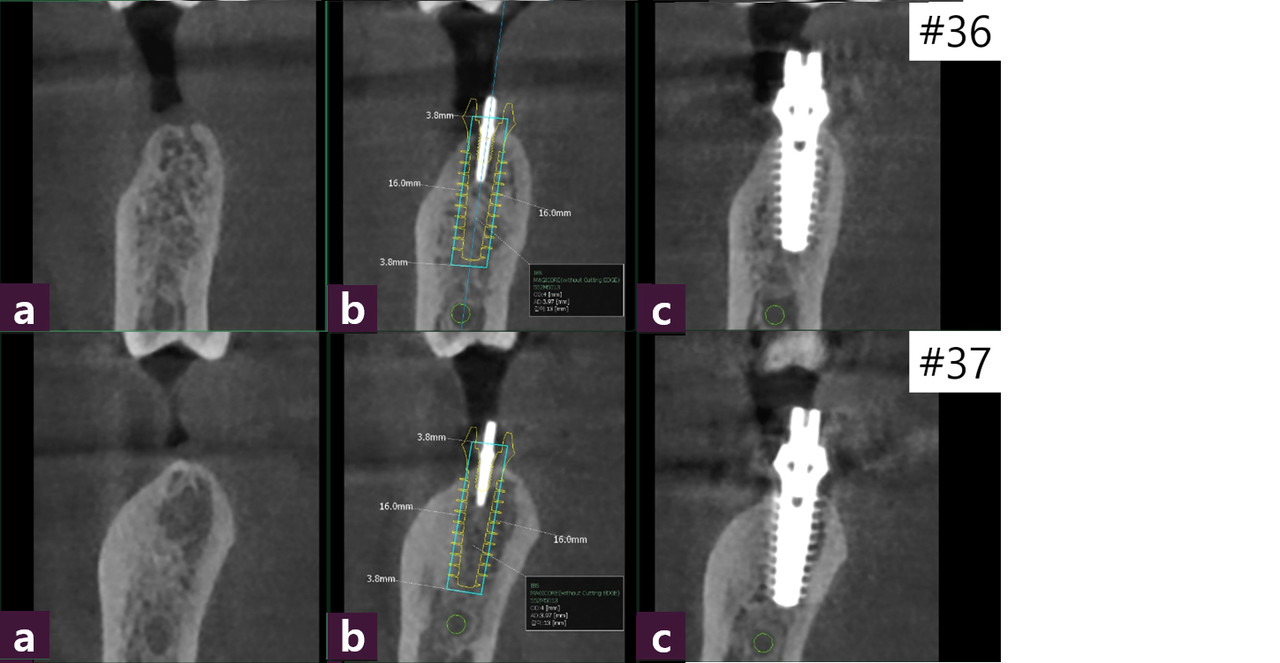

#36,37술전/후CT를통해 2년여의 장기간무치악 상태로 disuse atrophy로 의심되는 수질골(medullary bone)의 골질저하를 보였다 (그림5,6).

이것을 개선하고 빠른bone healing을 위해 MagiCore식립즉시 인상채득하여 교합되지 않는 비기능 임시치아로 splinting함으로써 저작, 연하 등의 정상기능 활동 시, 혀 와 협근의 압박에 의한 physiologic stimulation을 활용하고자 했다(그림7).

식립 2개월 후 abutment와 통상적인 Cr.이 하나로 결합되어 있는 Magic Cr.으로 최 종 보철하였다(그림8).

Ferrule (external connection)과dowel (internal connection)이 모두 금속으로 double connection 되어 있는 Magicconnection의 MagicCr.은 필자가 가장 선호하는 보철방 식이며 장기간의 사용시 cervicalchipping을 예방하기 위해 metalmargin을 두껍게 제 작한다.